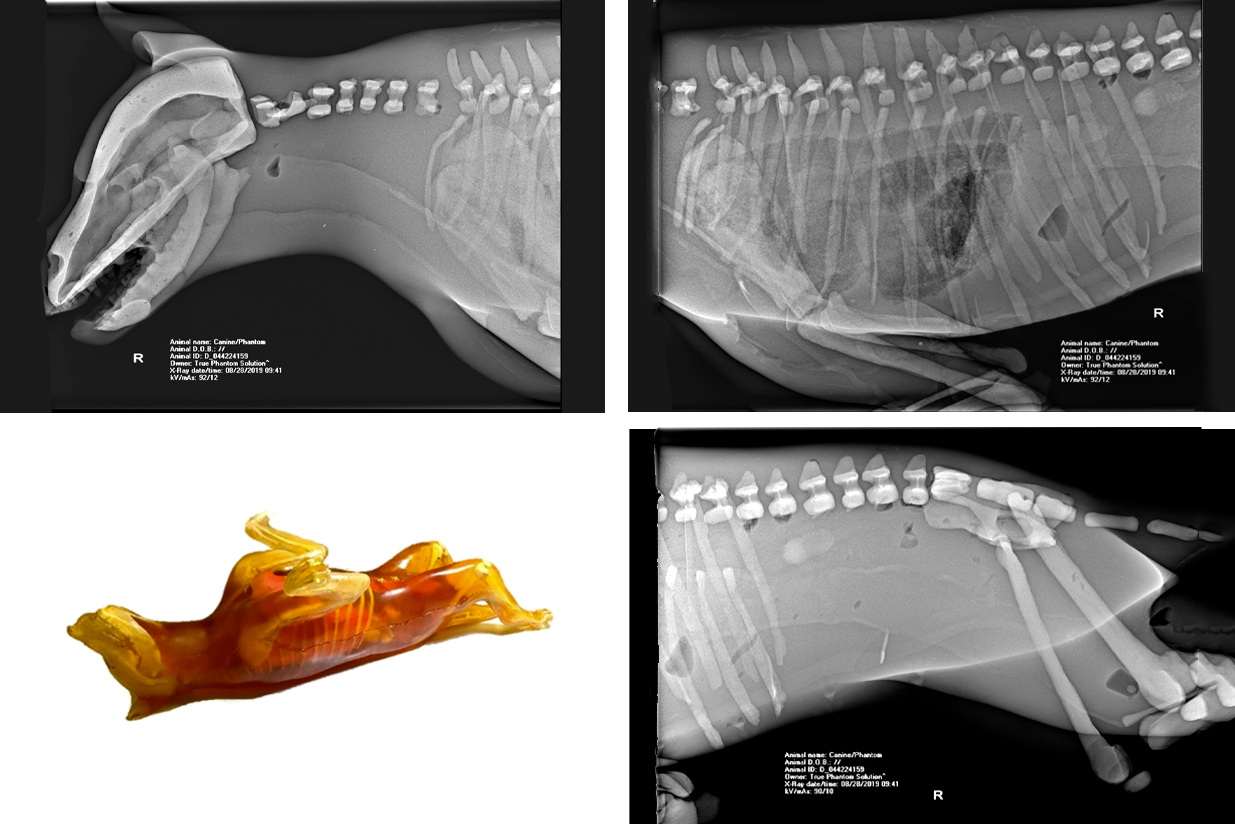

From morethansimulators.com

DOG PHANTOM FOR XRAY TRAINING More Than Simulators What Is A Phantom Dog Phantom poodles are poodles with dark coats and distinctive markings similar to a doberman. Apricot, brown, white, gray, black, cream, fawn. The phantom poodle is a variety of poodle that comes with a distinct color pattern on its coat, rather than a solid coat. There are many different types of phantom. Learn what a phantom poodle is, how it differs. What Is A Phantom Dog.